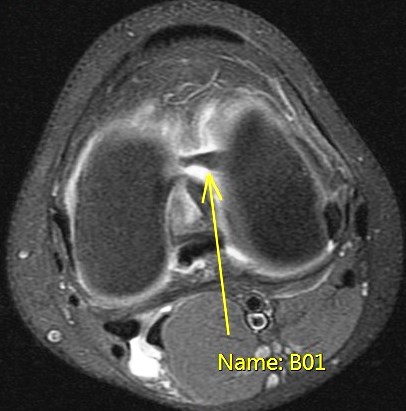

Figure 1 for case Unstable displaced lateral meniscus flap tear( RID2763 )

Figure 1

The flap is folded and displaced into the notch.

Unstable displaced lateral meniscus flap tear( RID2763 )